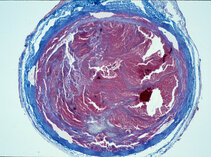

We are focusing our science momentarily on biocompatibility studies of novel biodegradable and resorbable materials such as biopolymers (i.e. PGLA) or trace elements such as magnesium or zinc potentially useful for the manufacture of vascular stents or stent grafts.

These images tell a story and we will explain it to you…..